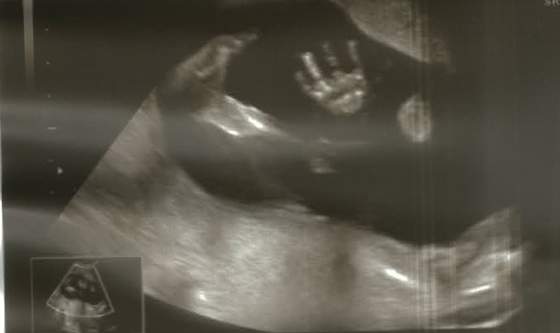

A na koniec pokazuje mi nogi i pyta czy sprawdzamy jeszcze płeć, ja mówię nie bo widzę, że jest to samo co ostatnio

miał wczoraj ubaw ze mnie. Ale mojemu mężowi, przeszło przez myśl, że może jednak się pomylił i będzie co innego.